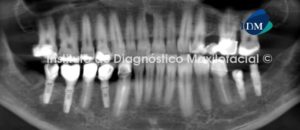

Paciente de sexo masculino de 66 años es referido al Instituto de Diagnostico Maxilofacial para la evaluación pre quirúrgica de implantes dentales en maxilar superior, el paciente refirió dolor intenso e “inflamación de encía” en la zona del cuadrante III, como dato clínico adicional la paciente refiere dicha sintomatología posterior a la cirugía de implantes dentales en el maxilar inferior. En la radiografía panorámica se observan estructuras óseas y dentarias de características aparentemente normales (Fig.1)